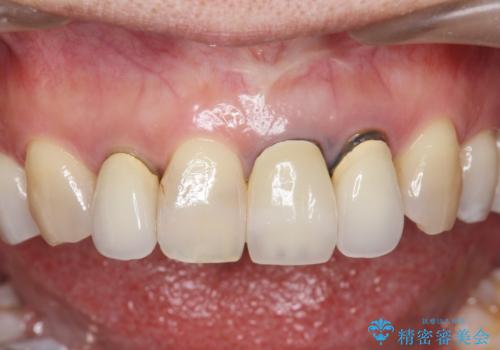

- 前歯のクラウンの歯肉の位置が年々変化し、歯ぐきのフチが黒くなってしまった、綺麗にしたいと希望されて来院されました。

装着されているセラミッククラウンを除去したのち、現在の歯ぐきのラインにしっかりと合う精度の高いオールセラミッククラウンを作製していきます。